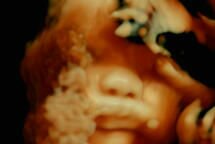

Stonewalling

VCH 2022. Regie: Huang Ji, Ryuji Otsuka. Mit: Yao Honggui, Huang Xiaoxiong

Der Mensch als Ware. Im wohl unzensierten Drama Stonewalling pfeift der eiskalte Wind des chinesischen Raubtierkapitalismus durch den Sommer einer unfreiwillig Schwangeren. weiter